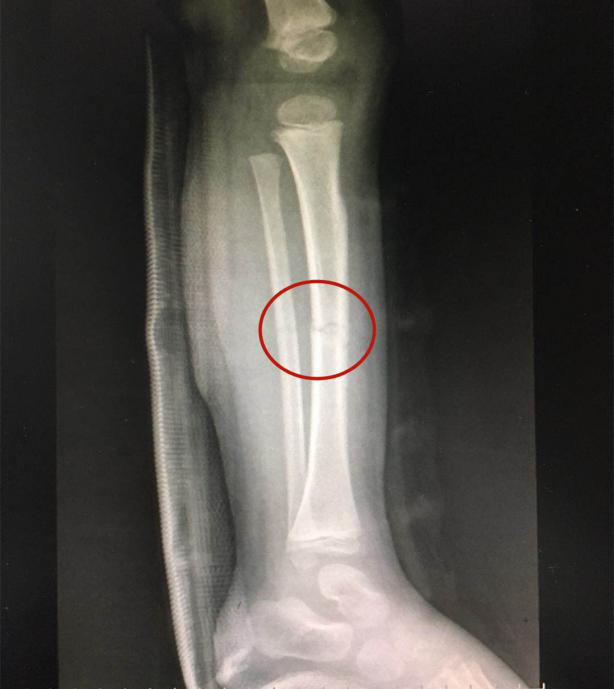

復位后,經(jīng)再次照X光顯示,患兒左下肢脛腓骨斷端緊密對合,外觀畸形得以糾正,手法復位治療非常成功。

手法復位后X片顯示脛腓骨斷端嚴密對合,左下肢中段畸形糾正